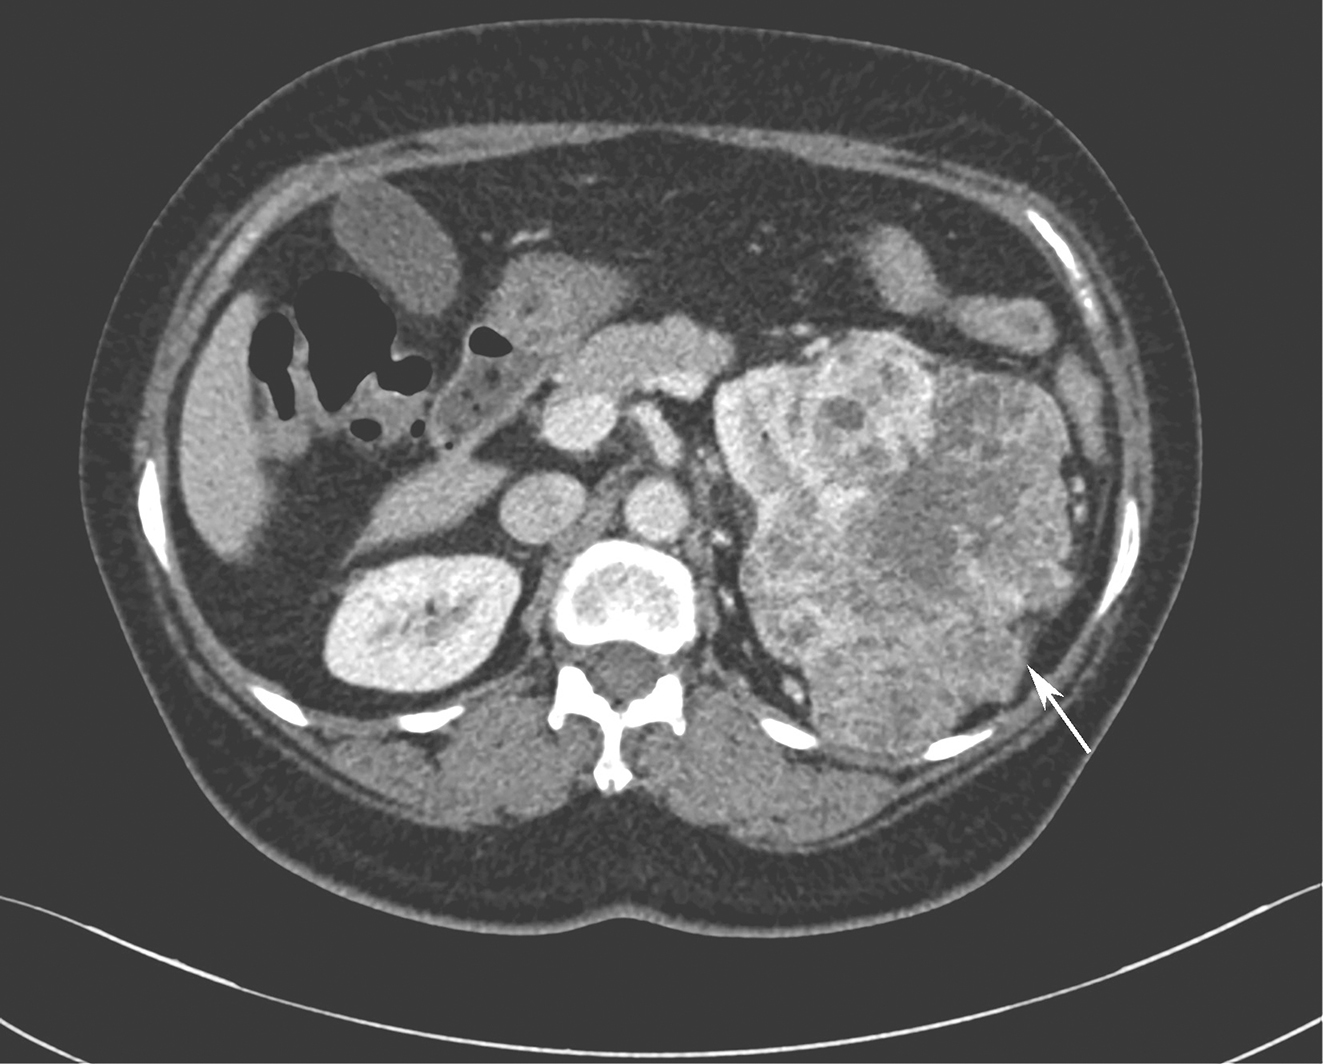

1小时条评论55岁女性,因左下腹反复疼痛2月余,加重1个月就诊。如何诊治? 【病例摘要】 患者,女性,55岁,因左下腹反复疼痛2月余,加重1个月就诊于四川大学华西医院。查体:下腹部触及8cmtimes;7cm包块,质韧,活动性差。 既往史及家族史 无特殊,家族中无类...